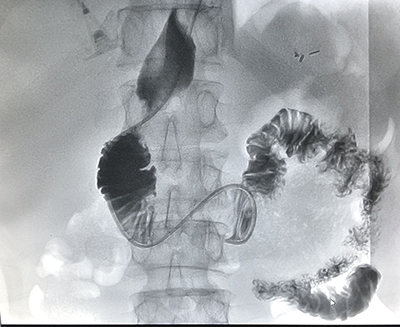

![]() | ![]() |

| (脾功能亢进的介入治疗) | (食道支架植入术) |